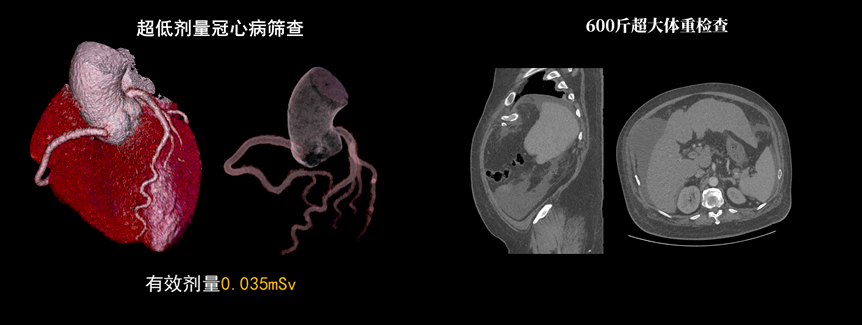

該設(shè)備除具備普通CT的功能外,還具備速度快、精度高、智能化、高效能、微劑量、大孔徑等優(yōu)勢。16厘米Z軸探測器、23毫秒時間分辨率,聯(lián)影天河640CT讓冠脈CTA檢查擁有“不選擇”的權(quán)利。搭載的一站式聯(lián)合掃描技術(shù),輔以便捷高效的后處理功能,AI精準(zhǔn)血管分割,自動預(yù)處理加載,逐支血管觀察,全時提效,可實現(xiàn)一次注射造影劑獲取多部位CTA、CTP和4D動態(tài)圖像,不僅可以助力腦卒中解決方案,還可助力腦血管畸形、腦動脈瘤等其他腦血管病的結(jié)構(gòu)和功能評估。

液態(tài)金屬軸承球管,陽極直冷技術(shù),提供30MHU球管熱容量,可高通量連續(xù)掃描。AI劑量調(diào)制、迭代重建等復(fù)合劑量控制方案,為體檢患者提供優(yōu)化劑量掃查。82cm大孔徑,讓大體型患者檢查更加舒適。

天河640CT的寬體探測器單圈掃描即可覆蓋全心臟,搭配快速機(jī)架轉(zhuǎn)速和獨家AI冠脈追焦技術(shù),可實現(xiàn)單心動周期內(nèi)無限心率、無限心律的冠脈成像,對于嚴(yán)重心律不齊、房顫、房撲,超高心率等情況,天河640CT都能在單心動周期內(nèi)獲得優(yōu)質(zhì)圖像。